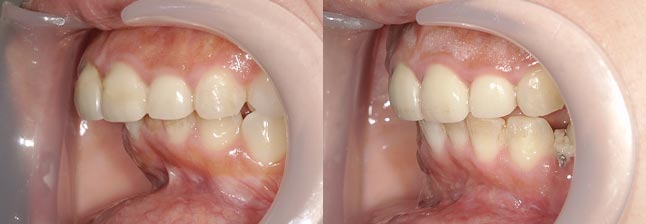

【治療内容】出っ歯、口元の膨らみが気になると当院を受診されました。上の前歯と歯茎が前方にポジショニングしており、下の前歯も歯茎から前に出ておりました。

<上下セットバック>

歯と歯茎を上は、5oバック、2oアップ、下は5oバックし固定しました。

※口ゴボ感が改善し、ご満足いただけました。

※afterは術後3か月時の写真です。

【費用】上下セットバック 2,307,800円(税込)

【リスク】感染・腫れ・出血・知覚鈍麻など